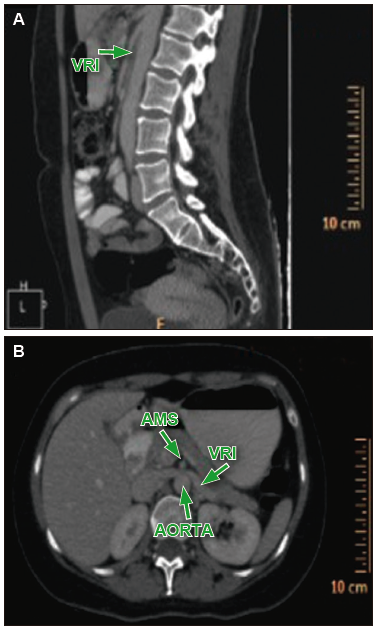

Figura 3. En el corte sagital (A) y axial (B) de la TC de abdomen con contraste, se

observa el estrechamiento del compás aorto-mesentérico que comprime la vena renal izquierda